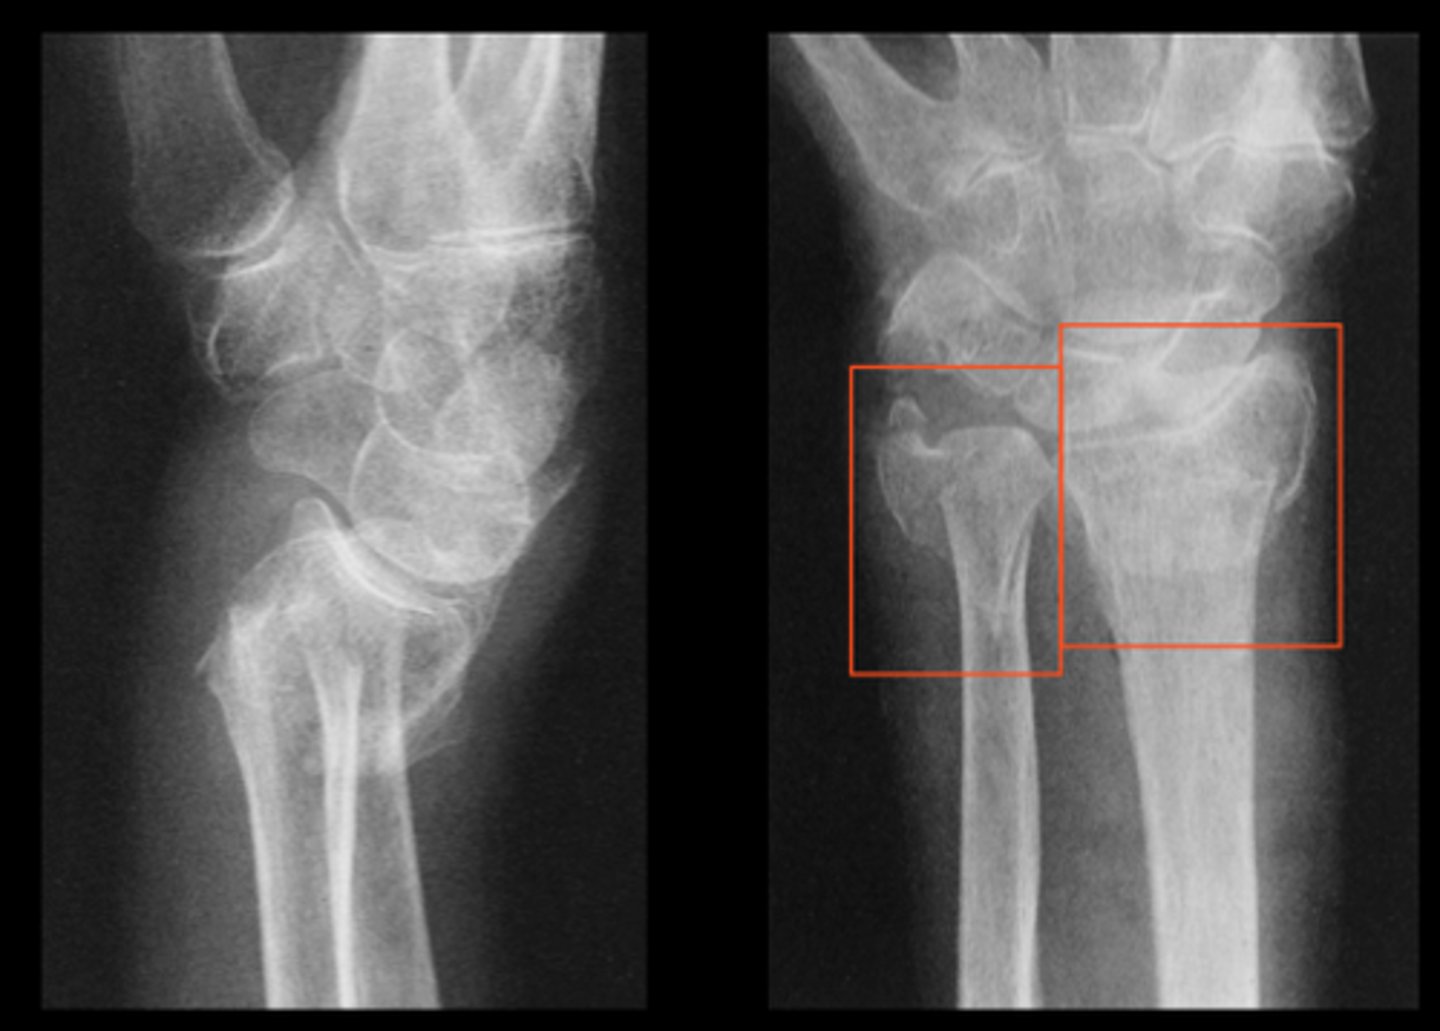

Colles fracture

distal radius is broken by falling onto an outstretched hand

Most common form of wrist

fracture from FOOSH injury

Distal radius displaced dorsally